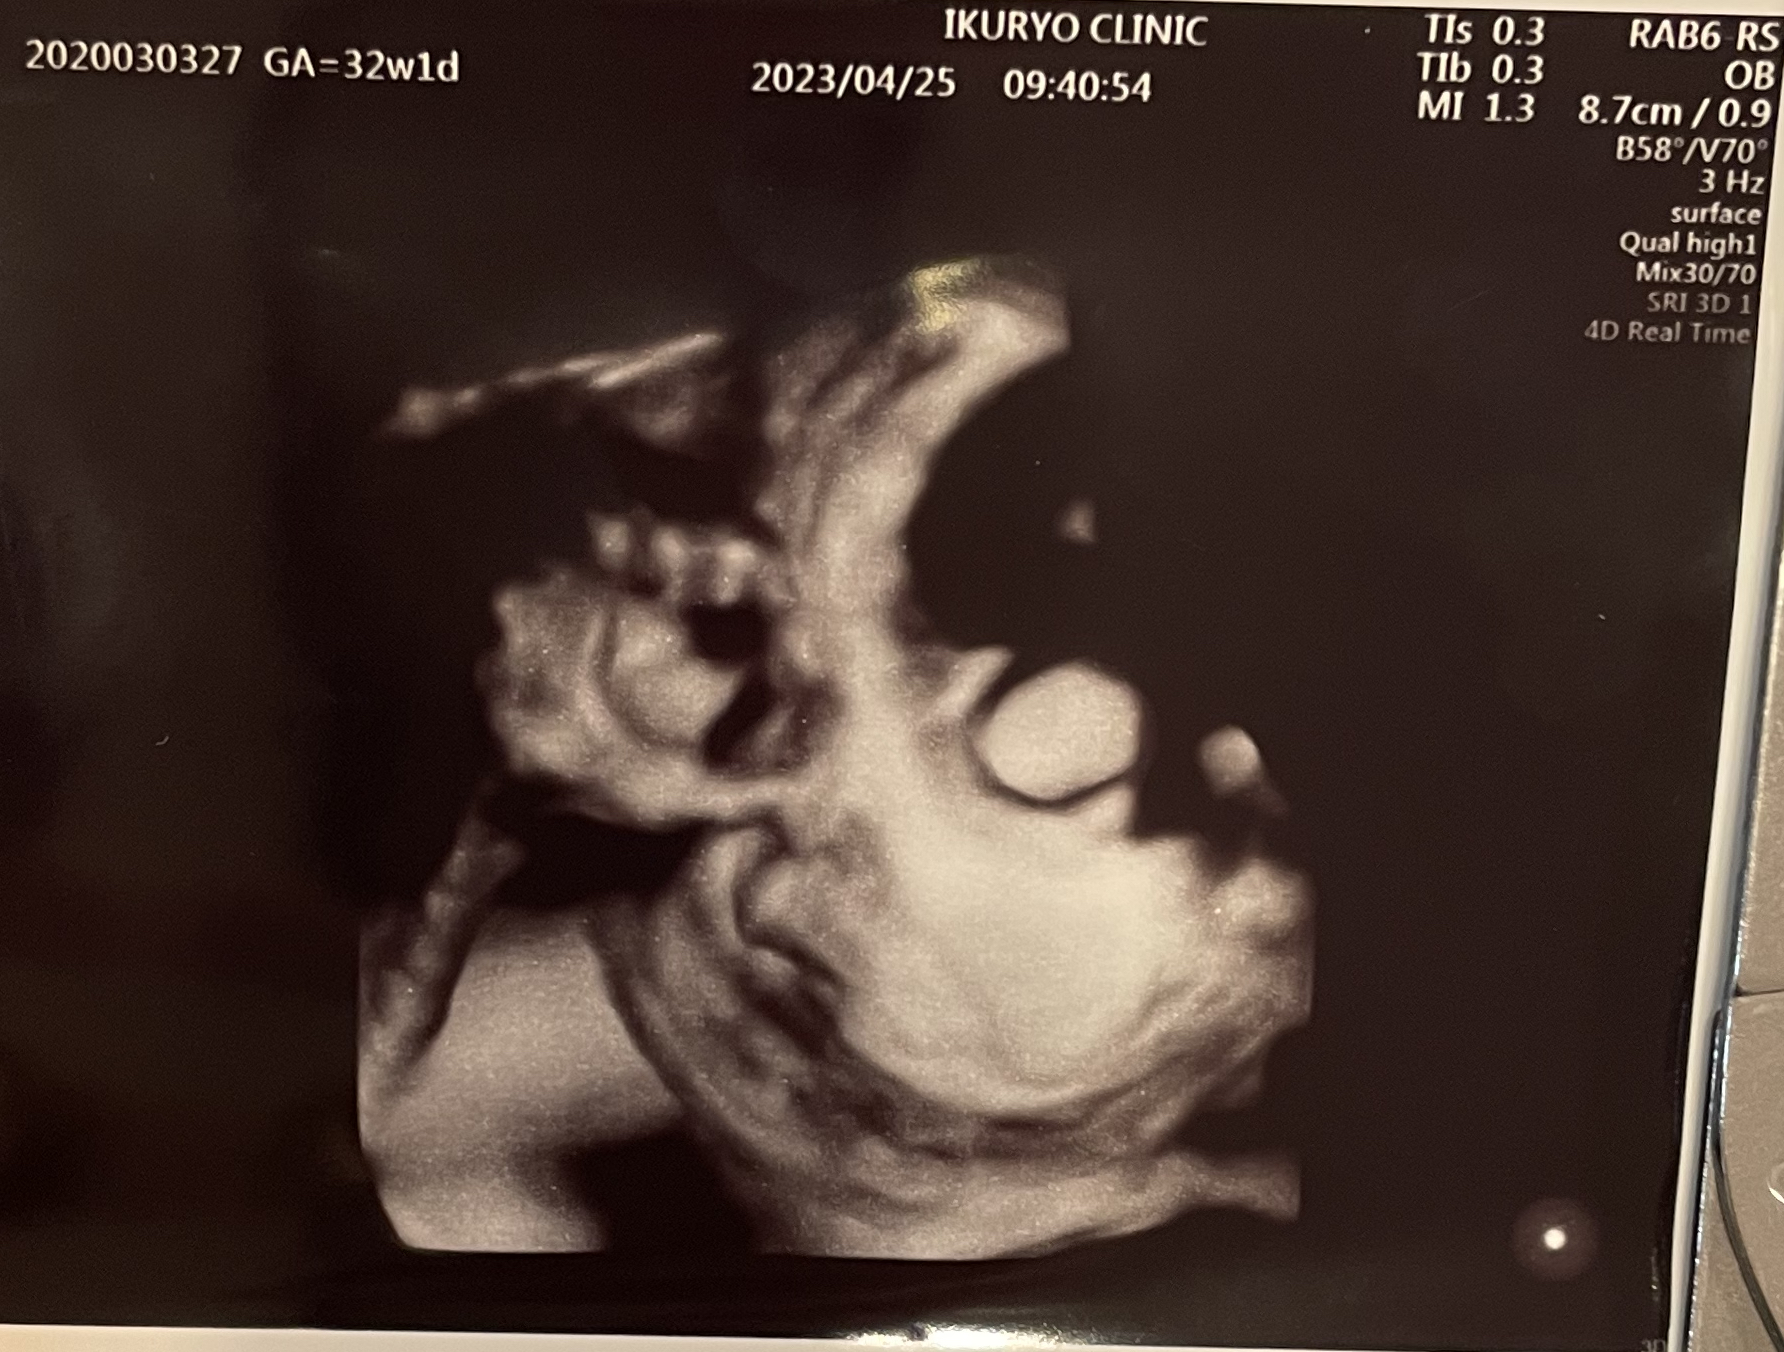

4Dのエコーでは、だいぶほっぺがぷっくりとしてきた様子を見ることができました。

いつも顔まわりに手を持ってきているのも可愛いです。生まれてからもそういう姿が見られたら、きっとより一層愛おしく感じるんだろうなぁ……と今からわくわく。